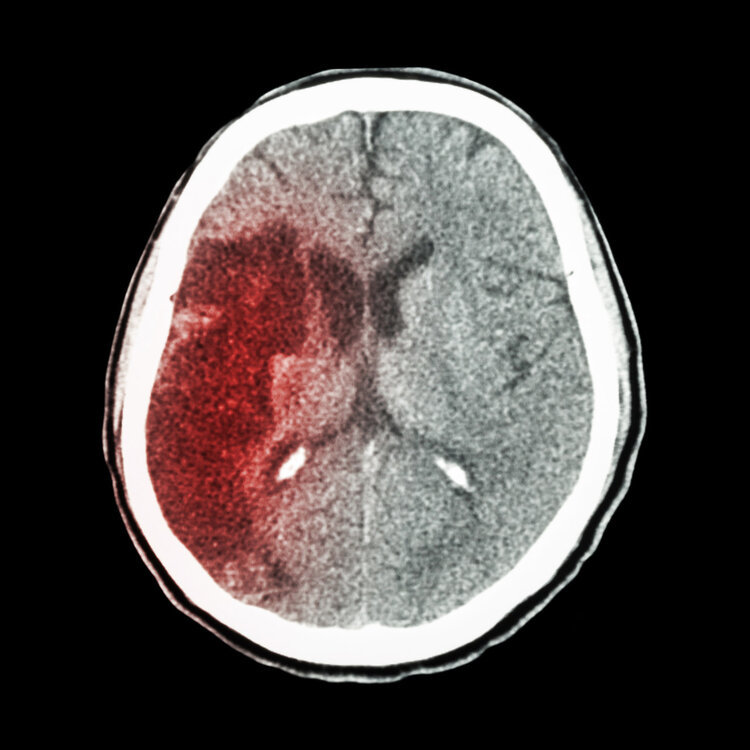

正常情况下,人体的动脉会根据身体的状况来进行工作,以满足身体的需要,如果血压控制不理想,会导致血管长期处于扩张状态,慢慢的失去弹性,进而引发血管破裂,压迫到脑组织,引发脑出血。

另外脑出血多数存在脑部细小动脉等破裂等的现象,因此可能会伴有麻木、乏力、失语等的一些症状。